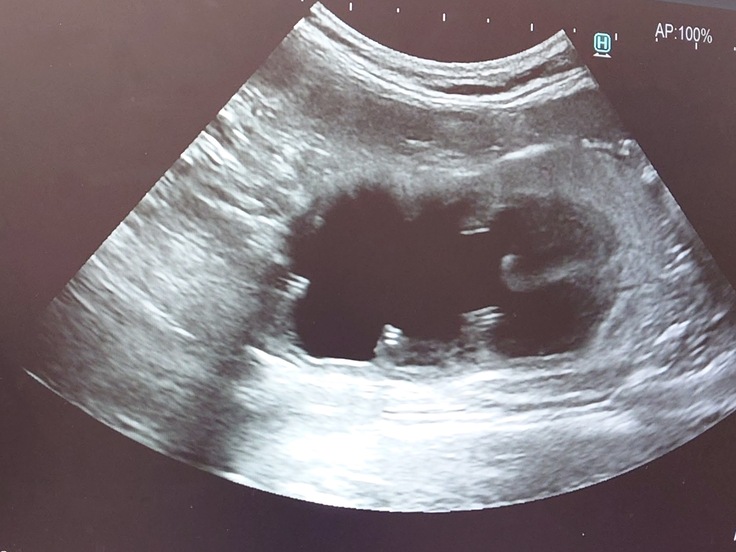

🐈かかりつけの動物病院でエコー検査をしてもらったら、相変わらず腎臓と腎盂が肥大したままだった。🐈

🐈おしっこは尿検査をしてもらって潜血+3で、蛋白質が1+。

血液検査も白血球の数値も高めでした。🐈

🐈市外の専門の動物病院でも検査してもらった結果、潜血4+と白血球の数値も高く、細菌もいるという結果で、おそらく尿路感染を起こしているのだろうということでした。🐈

ヨッちゃんは手術で尿管を切っていて短くなっているので尿路感染は起こしやすい状態であることと、術後も腎盂は小さくなることなく肥大したままなのでおしっこが本来は腎臓から膀胱に流れていかないといけないのに、あまりない症例だけどおしっこが膀胱から腎臓に逆流していることが考えられるかもしれないという説明を受けました。先生にヨッちゃんの症状で頻尿や多尿はありますか?と聞かれたので、トイレの回数や量は特に変わってなくておしっこの色が違う感じです。と、普段のおしっこの画像と、血尿が出た時の画像とヨッちゃんがトイレで踏ん張っている動画を先生に見てもらいました。

🐈頻尿や多尿だと膀胱炎の可能性が高いけどそれがないなら、おそらく腎盂腎炎になっていると診断を受けました。🐈